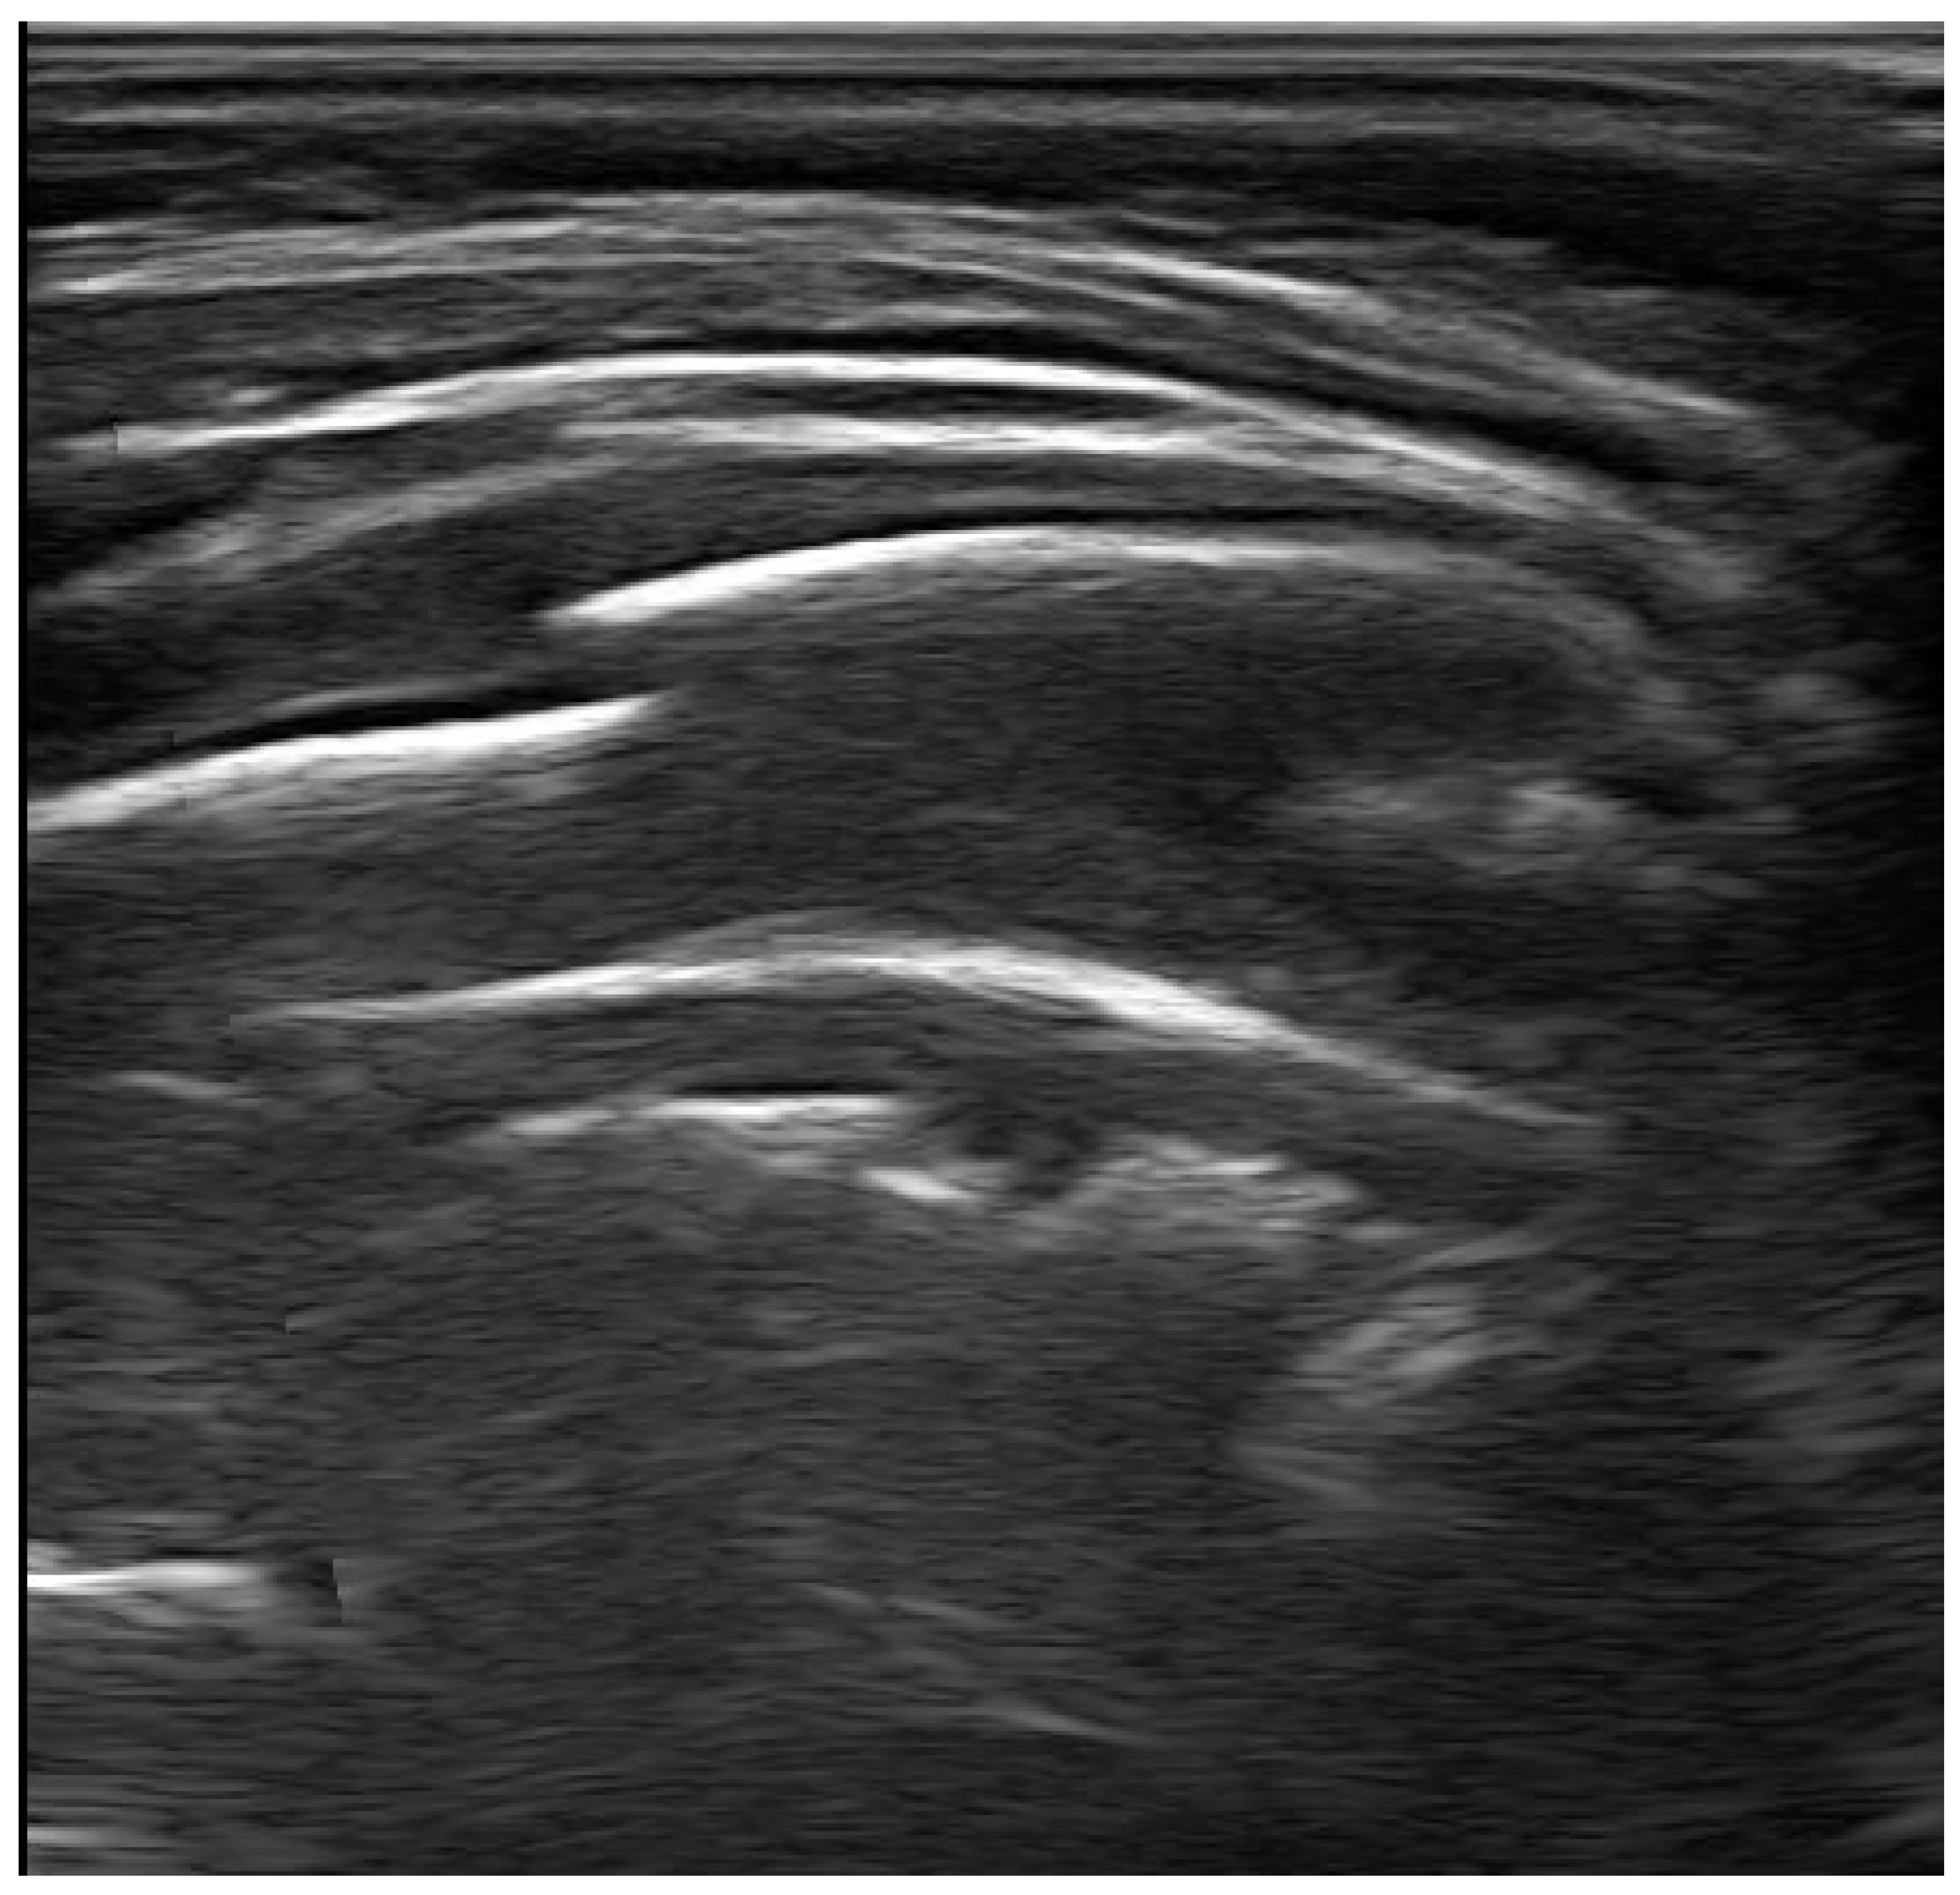

4.2. Pneumonia

4.3. Lung Abscess